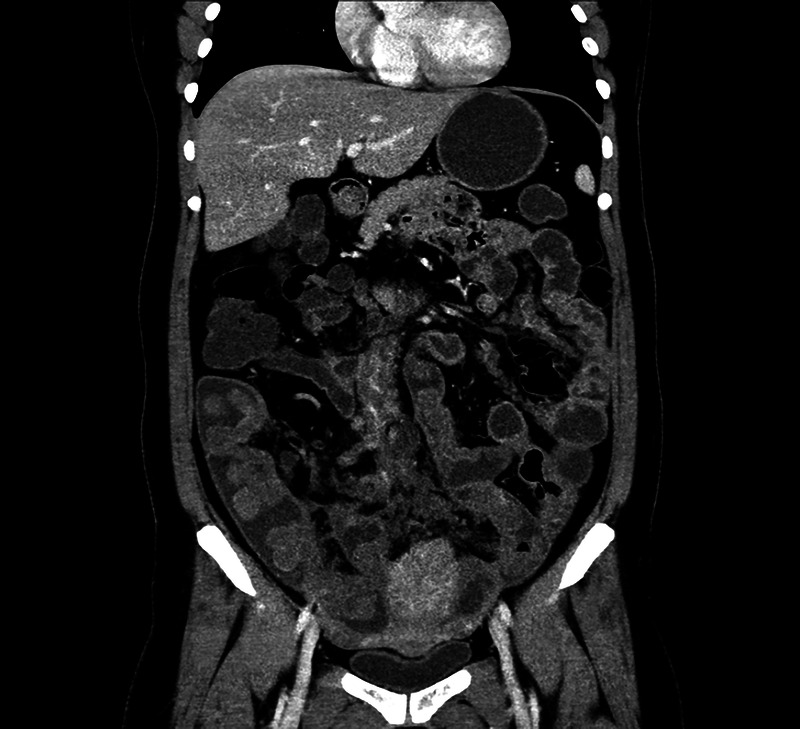

A rare but interesting case of small intestinal tumor diagnosed by transrectal EUS-FNA (with video).